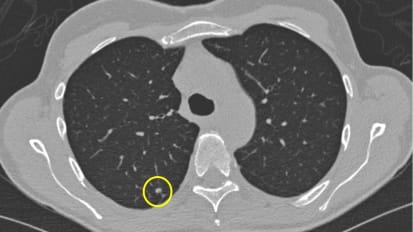

Gene signatures derived from lung carcinoma could potentially predict outcomes among individuals with small lung cancers detected by chest CT imaging, when those tumors cannot be distinguished visually as aggressive or indolent.

Building a Hub to Catch Lung Cancer Early

Fewer than 10 percent of potentially eligible patients undergo lung cancer screening, resulting in unnecessary illness and death. The new Chief of Pulmonary, Critical Care and Sleep Medicine at Mount Sinai Morningside wants to change that.

Decline in Lung Cancer Deaths Is Linked to Increased Screening

A recent, substantial decline in lung cancer deaths is associated with earlier diagnosis of lung cancer than in the past, a new study shows.

A recent, substantial decline in lung cancer deaths is associated with earlier diagnosis of lung cancer than in the past, supporting the need for increased use of screening to save lives, according to a Mount Sinai study published in JAMA ...

Lung screening at Mount Sinai leads to early detection of lung cancer in former smoker

Growing up in Austria, Wolfgang Lehner was a heavy, pack-a-day smoker from age 15 to 51. He quit smoking in 2010.

Lung Cancer Screening Dramatically Increases Long-term Survival Rate

The results show that patients diagnosed with lung cancer at an early stage via CT screening have a 20-year survival rate of 80 percent.